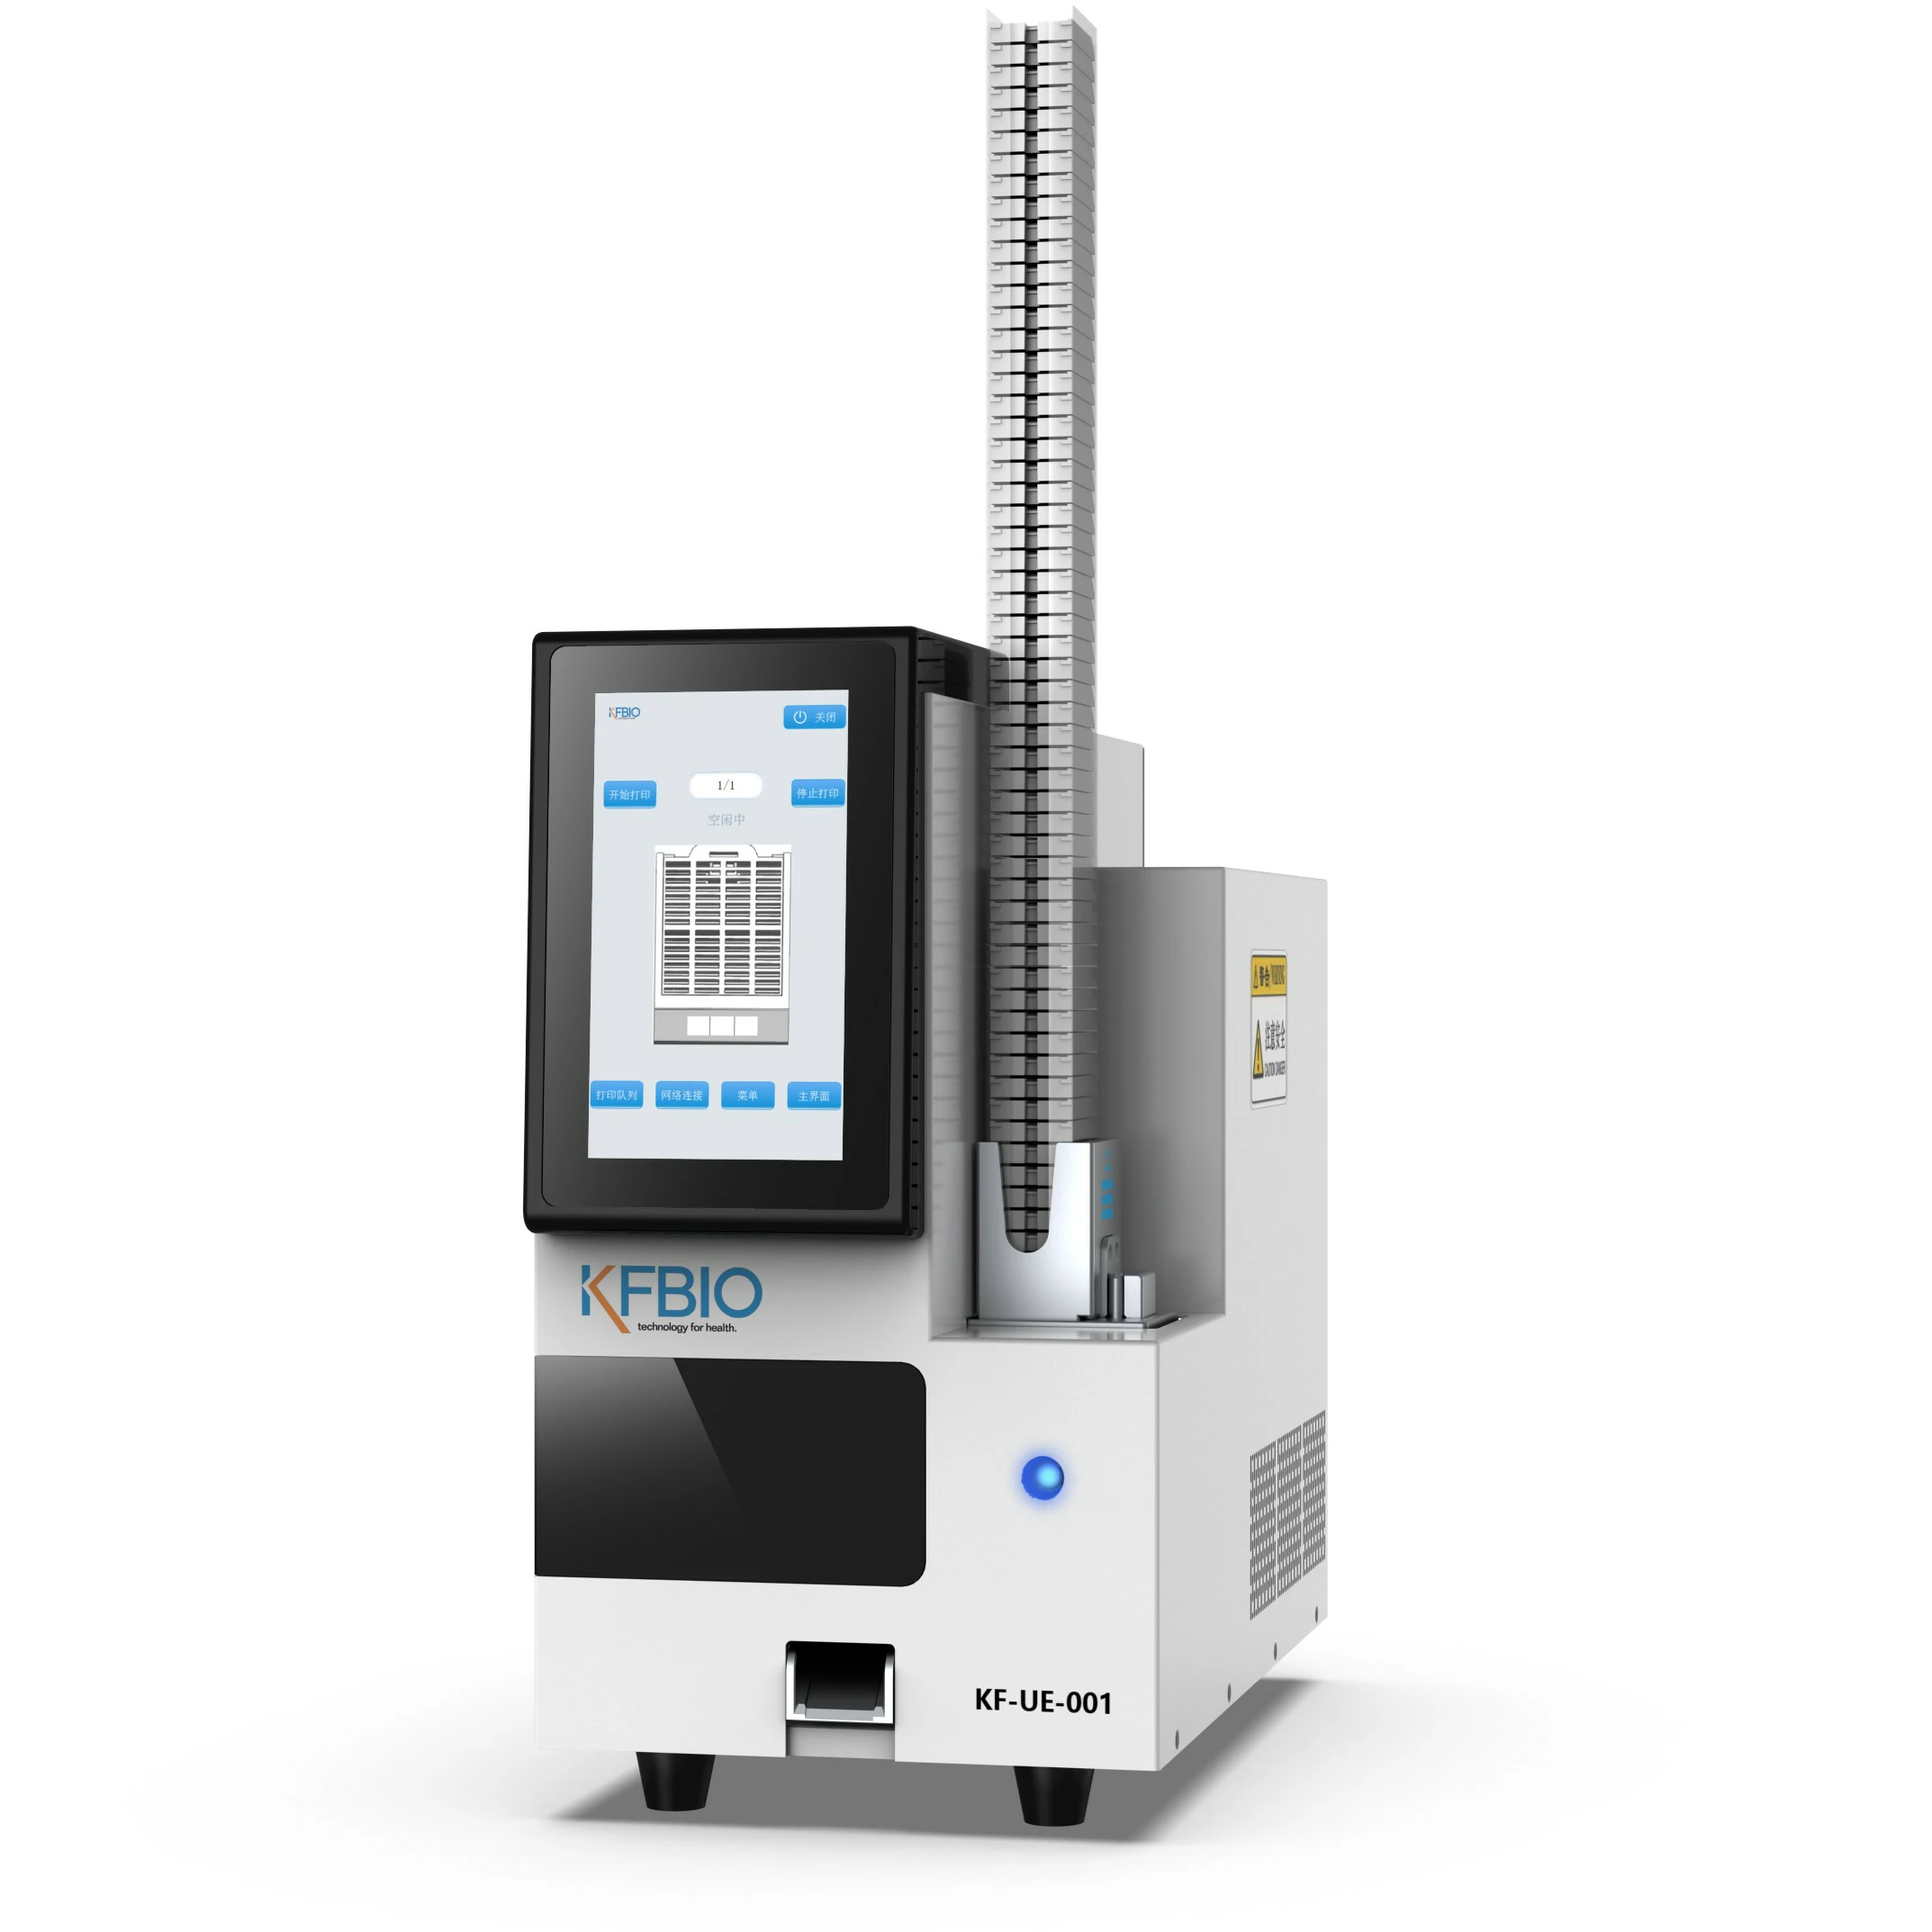

KF-FL-005

Digital Pathology 5

Slides Scanner fluorescence

Fast, High-precision,Stable, Clear

Scientific research, clinic,

tumor micro environment